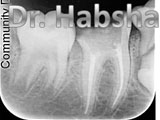

Clinical Work Photos

What We Do

Dental Services